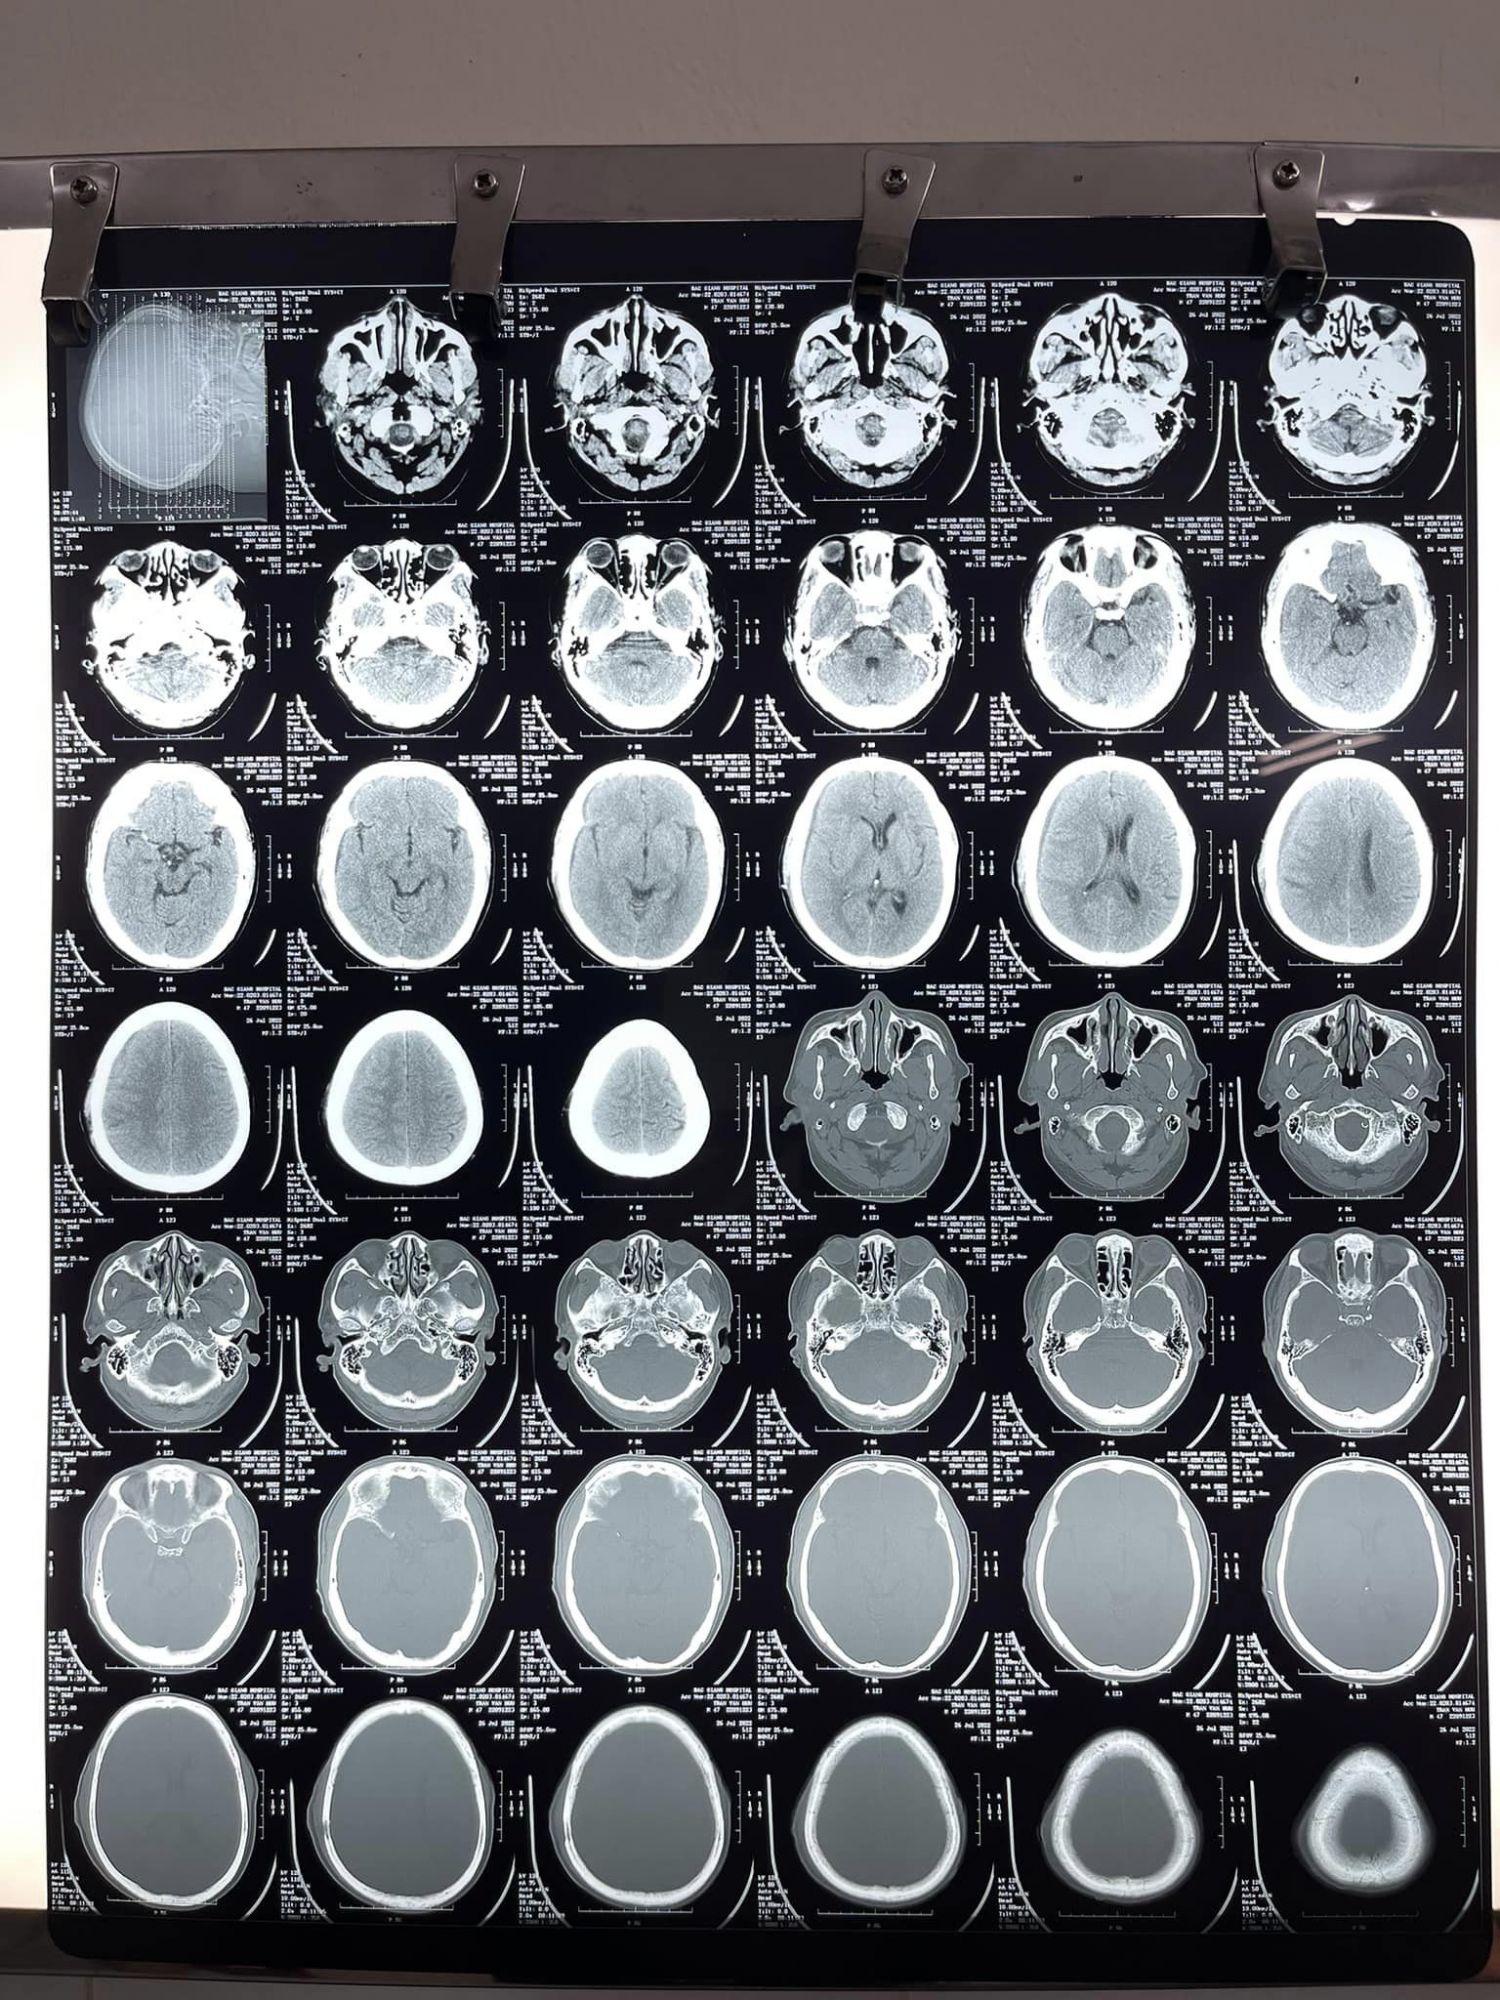

Tại đây, sau khi được bác sĩ thăm khám và làm các cận lâm sàng, ông H được chẩn đoán chấn thương sọ não, tụ máu dưới màng cứng não bán cầu phải trên nền bệnh nhân tăng huyết áp và đã chạy thận nhân tạo chu kỳ 14 năm. Nhận thấy đây là một ca bệnh khó, phức tạp, các bác sĩ đã tổ chức hội chẩn liên chuyên khoa: Ngoại thần kinh, Nội tim mạch, Nội thận TNLM, Hồi sức tích cực- chống độc, Phẫu thuật gây mê – hồi sức và đi đến thống nhất tiếp tục điều trị tích cực cho bệnh nhân. Sau vài ngày điều trị, nhận thấy tình trạng người bệnh tiến triển nặng, khối máu tụ to lên gây ra sự chèn ép lên não và đe dọa tính mạng của người bệnh nếu không được can thiệp kịp thời. Ngay lập tức, một cuộc hội chẩn mới giữa các chuyên khoa liên quan đã diễn ra và nhanh chóng, bệnh nhân có chỉ định phẫu thuật lấy máu tụ dưới màng cứng bán cầu não (P). Kíp mổ gồm Bs.CKII Mạc Hoàng Dương - Trưởng khoa Ngoại thần kinh, mổ chính cùng Ths. Bs Dương Văn Tuyên. Ca mổ gặp khó khăn khi người bệnh có nguy cơ rối loạn đông máu, diện đông máu rộng, yêu cầu người phẫu thuật viên phải thao tác nhanh, chính xác, khéo léo không để chạm vào mạch máu ở vỏ não. Sau 2 giờ đồng hồ, bằng kinh nghiệm, đôi bàn tay khéo léo và sự tập trung cao độ, kíp mổ đã cố gắng lấy tối đa máu tụ trong màng não, cứu sống người bệnh. Chỉ 1 tuần sau mổ, tình trạng người bệnh tốt lên nhanh chóng, vết mổ khô, liền tốt, kết quả chụp CT scaner sọ não kiểm tra sau mổ tốt. Sau 10 ngày phẫu thuật, bệnh nhân đã ổn định, trở lại sinh hoạt bình thường, được các bác sĩ cho xuất viện về nhà và tái khám theo hẹn.